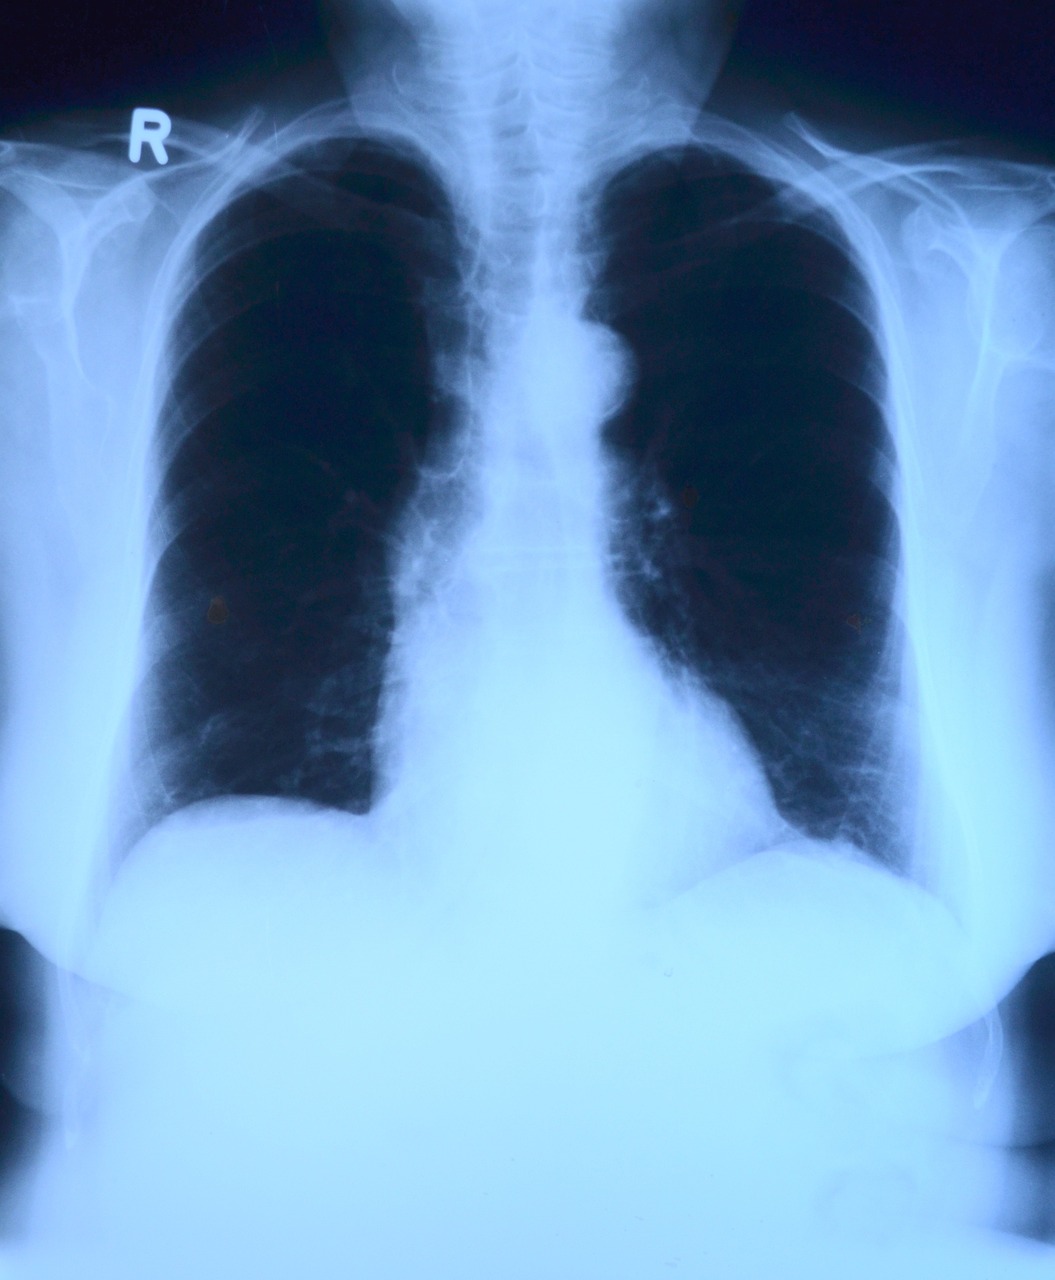

2) 구별법

- 흉통 및 가래 색의 변화.

- 청진 시 비정상적인 폐음(크랙클 소리).

- 흉부 X-ray로 확진.